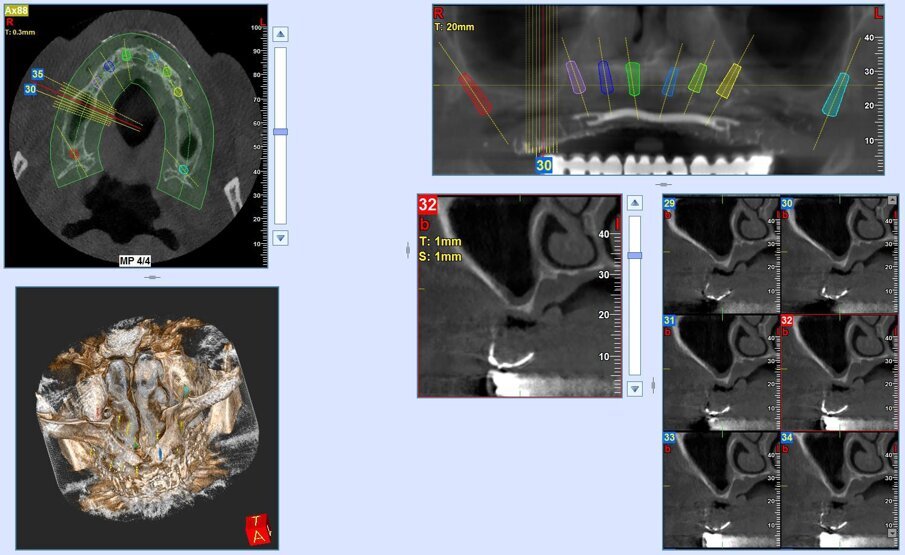

Inoltre l’aiuto della chirurgia navigata, consente di posizionare gli impianti in una posizione pianificata in precedenza ben distribuita lungo l’arcata, limitando al massimo i disparallelismi e semplificando le fasi protesiche.

Gli impianti vengono distribuiti lungo tutta l’arcata cercando il parallelismo e limitando il più possibile i cantilever (6-7 impianti superiori e 5-6 impianti inferiori). La scelta di utilizzare i monconi dritti (grazie al parallelismo degli impianti) è da preferire in quanto quest’ultimi sono anche i più robusti e resistenti nel tempo al carico assiale; inoltre caricano l’impianto lungo il suo asse limitando i carichi disassati. Una volta elevato il lembo mucoperiosteo ed evidenziato l’osso alveolare o basale, attenzione deve essere fatta nel fare un’ostectomia riduttiva mediante una fresa a palla del diametro di 0,6-0,8 cm per creare un piano più uniforme possibile tale da formare una piattaforma d’osso alla stessa altezza, guadagnando anche spessore V-L ed uniformità. Gli impianti devono essere posizionati alla stessa altezza tra di loro e distanziati in maniera tale da favorire le manovre di igiene orale inter-implantare. Una volta posizionate le fixture sottocrestali (1-3 mm) come descritto, vanno connessi i monconi solitamente con collare mucoso di 3-4,5 mm in altezza, ponendo particolare attenzione che i tessuti molli suturati non coprano la parte di accoppiamento conometrico. Verificato il parallelismo corretto dei monconi mediante i pin parallelizzatori, siamo certi che l’accoppiamento e la disconnessione delle cappette contenute nella protesi potrà avvenire nel miglior modo possibile senza creare tensioni.

- Pozzi A., Hansson L., Carosi P., Arcuri L. Dynamic navigation guided surgery and prosthetics for immediate loading of complete-arch restoration. J Esthet Restor Dent. 2021;33:224-236.